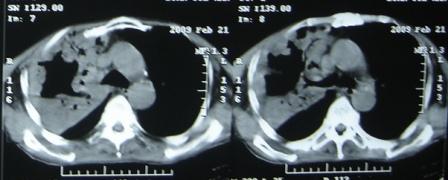

xx 男 63岁 发热 家属描述有时高热 有时低热 抗酸杆菌阴性 于2月21号 胸片及ct

3月10号复查